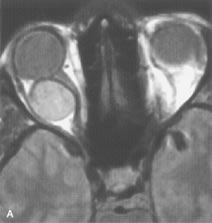

Metastatic Tumors

Breast carcinoma metastatic to the orbit has been demonstrated to be hypointense to the surrounding orbital fat on T1-weighted studies and hyperintense on T2-weighted images and has an affinity to the extraocular muscles (Fig. 20).50,64 The MRI characteristics of prostate carcinoma metastatic to the orbit have been described as involving the greater and lesser wing of the sphenoid, orbital roof, and optic canal. Diffuse bone hypertrophy with isointense or slightly hyperintense tissue on T1-weighted images represents the osteoblastic carcinomatous bone infiltration. Contrast enhancement is variable on T1-weighted and fat-suppressed images.65

Fig. 20. A. T1-weighted MR scan demonstrates nodular enlargement of both medial rectus muscles (arrows). B. T1-weighted fat-suppressed contrast-enhanced scan confirms the presence of small metnstatic deposits within the muscles (open arrows).